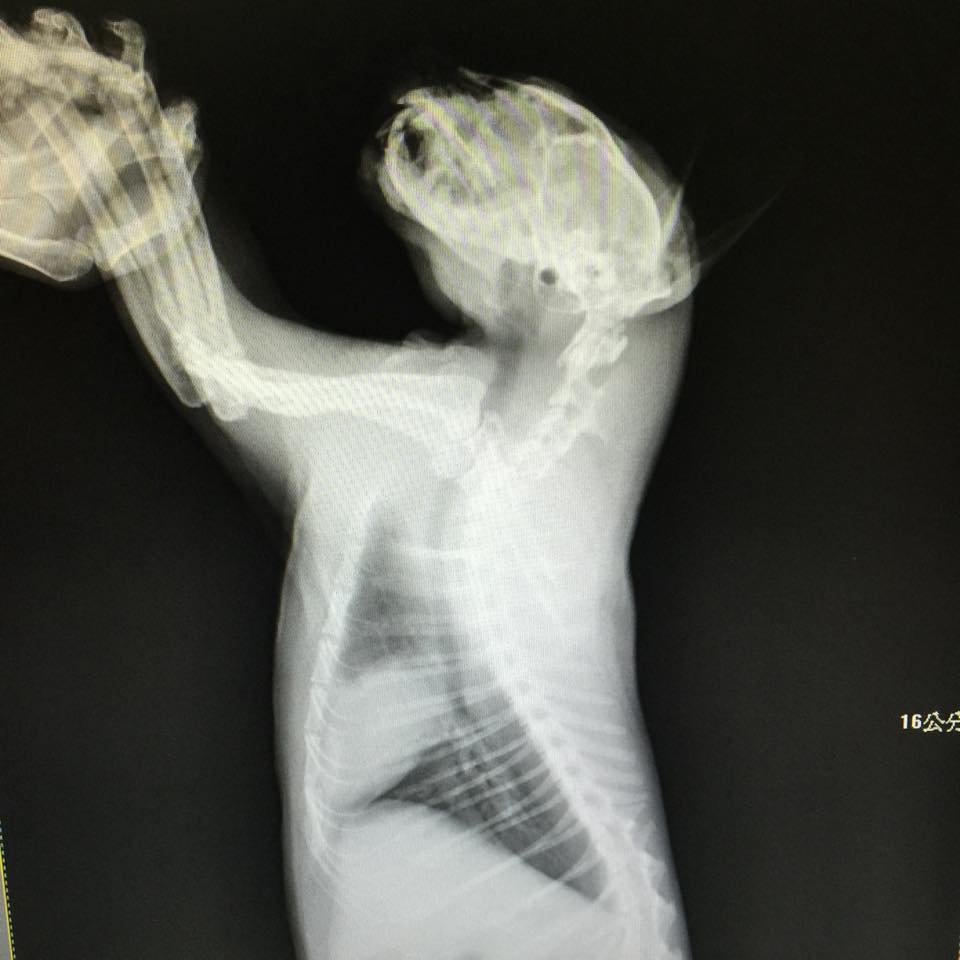

主題: 疑似車禍,下巴鮮血直流,呼吸很喘很用力,眼睛似乎看不到人 申請者姓名: 陳許鳳純 花色: 申請日期: 2015-06-24 19:27:56 申請者部落格: 申請者臉書網址: https://www.facebook.com/profile.php?id=100001818976639 所在縣市/合作醫院: 台東縣/寶佳動物醫院 治療費用: 15550元 需求人數: 17人 已結案 (2022-04-14 17:48:19) 報名人員: 如絲(已付款)、Ashley Lo(已付款)、Eligh Liu(已付款)、Joe Chen(已付款)、火鳳貍 x3(已付款)、陳鳳 x2(已付款)、Ting Huang(已付款)、舊椅子(已付款)、Mai Lin Lai(已付款)、Jefftorah(已付款)、茶茶(已付款)、櫻花妹(已付款)、迷迷(已付款)、Frankie(已付款)、 候補人員: 動物病情說明: 我的餵食區有隻浪浪好多天不見,我拜託一位住在附近的大姐幫我留意,近午(06/09)大姐來電說有看到那橘白貓,倒在牆邊草叢,我趕緊抽空出去看,沒錯,是牠! 疑似車禍,下巴鮮血直流,眼睛似乎看不到我, 呼吸很喘很用力。緊急送醫,診斷出:浪咪疑因車禍造成牠的下顎嚴重骨折,單眼沒有反射,還有腦震盪,呼吸很喘很用力,鼻骨也有骨折,單眼因腦部撞擊,目前已喪失視力,貧血及血小板過低,剛住院時醫師先以控制腦部撞擊及肺部出血,投降腦壓的藥、點滴、補血鐵劑、抗生素,先腦壓控制下來,再擇日施以手術:下顎骨折矯正手術及結紮。下顎手術完成時,有用鼻胃管餵食二天,後再用針筒餵食,再慢慢讓浪咪自行吃罐頭及飼料。鼻餵管拿掉後,餵浪咪軟濕食及寵善,胃口還不錯,飼料不大愛吃;在住院約第6天起,醫師會讓浪咪在病房外走路自由活動一下。 動物近況說明: 浪咪我帶回家照顧,不忍心原放了:因腳神經係,終其一生走路會一跛跛的,但不會影響浪咪走路的功能,至於下顎處,還要再花一些時間修復,現在還是會偶而流口水,下巴處還有一些濕濕的,醫師說過些時間會好的。浪咪雖是公貓但很親人也很腮奶,一直在我身邊磨蹭,目前跟我一起睡,因為家裡貓多,還是暫時要隔離一段時間才好~浪咪的費用還是要麻煩各位幫忙,感謝您~